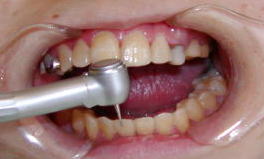

A開口障害と歯科治療

ショートのバーと、ショートヘッドのハンドピースを使用します。

開口器の使用は最小限にとどめ、休みをとりながら歯科治療を行います。

上から、22mm、18mmのタービン 上から、14mm、13mm、9mmのタービン。